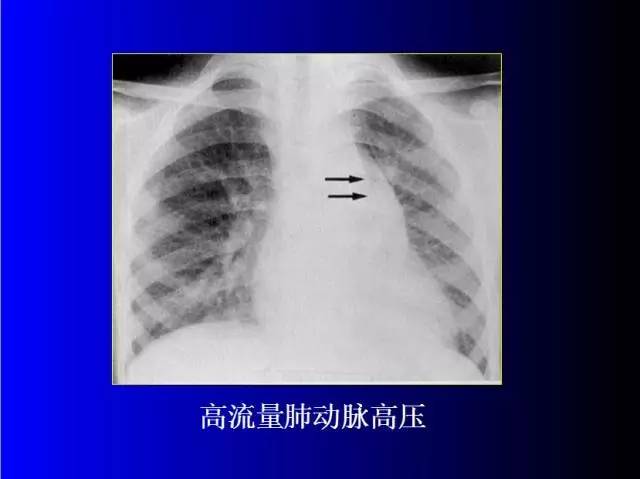

肺部基础X片及CT片解读